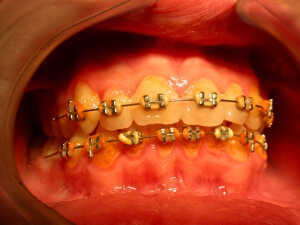

Except for the bad oral hygiene, gingivitis is related to hormonal changes during puberty or pregnancy, or the presence of orthodontic mechanisms in the mouth that make difficult to maintain good oral hygiene.

Interceptive Orthodontics

There are ways to prevent orthodontic problems and avoid braces. It’s essential to check our children early and on a regular basis, to avoid teeth crowding, discontinue a bad oral habit, or in order to guide favorably the facial and dentoalveolar development.